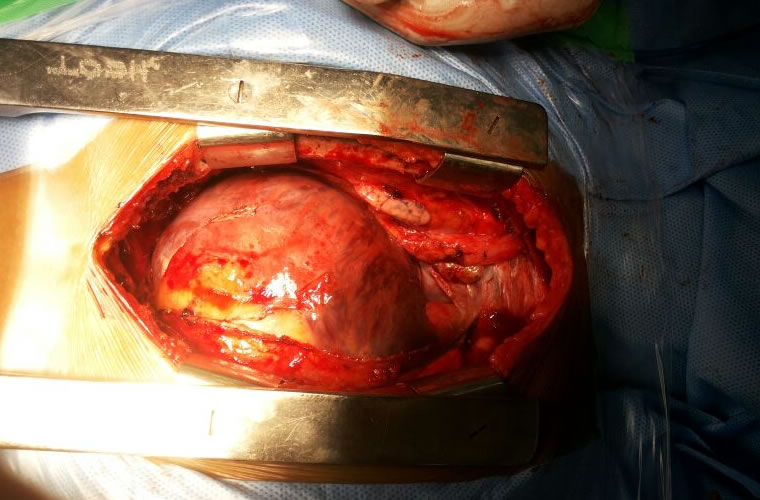

Dr.DineshShanmugaSundaram is specialized himself in each & every part of Cardiovascular & Thoracic Surgery both in Adult & Paediatric or Congenital Heart Diseases. He is both an ethical & academic surgeon,changed the trend in Cardiac Surgery to fast & safe level, as prolonged procedures in Cardiac Surgery increases postoperative complications. We aim at decreasing perioperative complications to the maximal level. Read More